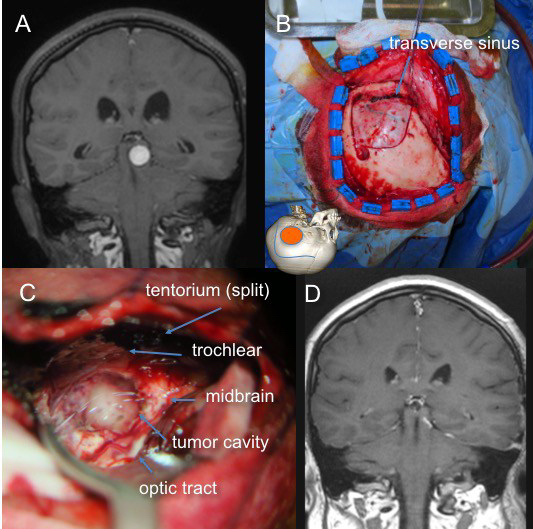

la voie sous-temporale trans-tentorielle

donne accès à la face latérale du mésencéphale et de la protubérance ; elle est limitée par le complexe des veines de Labbé ; elle peut être étendue vers le bas par l’ouverture de la tente du cervelet. elle est limitée en haut par la bandelette optique.

abord sous-temporal trans-tentoriel

pour les lésions qui affleurent à la face latérale de la protubérance, elles peuvent être abordées latéralement par voie sous-temporale transtentorielle.

la section de la tente du cervelet apporte un angle de vision satisfaisant pour contrôler la partie basse de la lésion.

la dissection minutieuse des vaisseaux (artère cérébelleuse supérieure et veine basale) et du nerf trochléaire donne accès à la région en arrière de l’émergence du trijumeau.